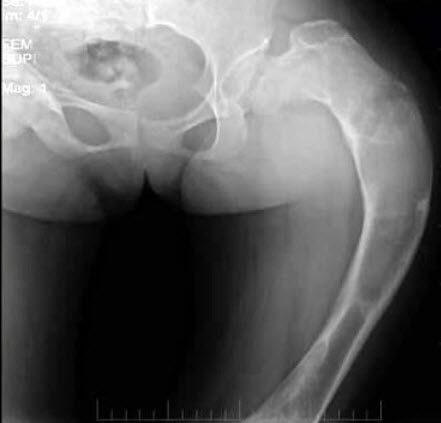

61、单项选择题

男,64岁,咳嗽、高热数日,无痰中带血,X线检查如图,最可能的诊断是()

A.右侧胸腔积液

B.右侧胸腔积液并肺脓肿

C.右肺炎

D.右肺不张

E.气胸

62、问答题 简述正常乳腺导管造影所见?

63、单项选择题

男,根据其正常骨盆影像图像,判断其最可能的年龄()

A.5岁左右

B.10岁左右

C.15左右

D.20岁左右

E.25岁左右